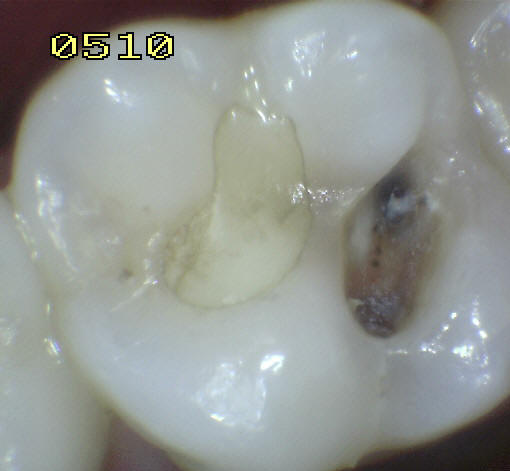

3 |

Restauración color

diente |

|

4 |

Amálgama |